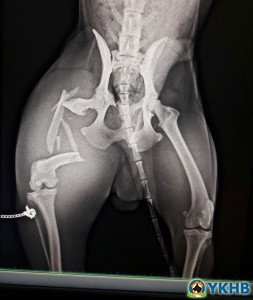

Yaralılar için destek

Hangi birinin ilanını yapayım o kadar çok trafik kazası yaralı , şiddet görmüş, tekmelenmiş , üzerine yakıcı sıvı dökülmüş  hayvan geliyor ki ilan yapmaya bile vakit bulamıyorum. Tek vakit bulunduğum şey hemen kliniğe yollamak ve tedavilerini yaptırmak. Allaha şükür tedaviye tanıt verip iyileşen çok çok fazla. Kayıplar tabii ki oluyor ama kaderine bırakmayıp borç harç tedavi ettiriyoruz. Klinikte kara kaplı borç defteri iyice şişti. Bu gün artık derdimi anlatma zamanı geldi diye düşündüm.

Dertler paylaştıkça azalır. Ameliyat olan hastalar için ilave olarak ameliyat MASRAFLARI üzerine bir de pansiyon parası ödememek için ilaç tedavisine barınakta devam ediyoruz o nedenle de ilaçlara da ihtiyacımız oluyor. Ben dikkatinizi çekti ise ender olarak destek isterim çok zorda kaldığım da. Ancak, bugünler de o zor zamanlarımız. Sizlerden destek bekliyoruz ilaç olabilir ameliyat masraflarıma sponsor veya katkı olabilir.